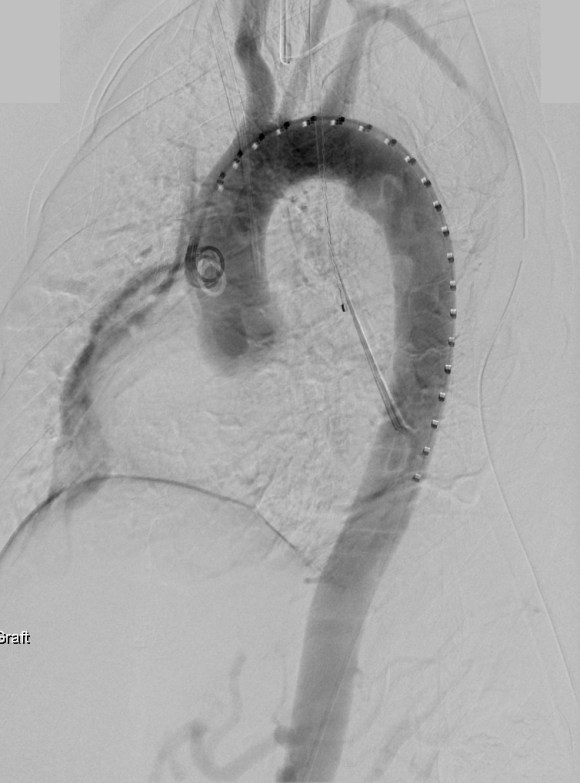

The patient was operated on in a hybrid endovascular OR suite. A right groin incision was made to expose the common femoral artery for endarterectomy and left common femoral access was achieved for angiographic access, but also to place a wire across the occlusion into the common femoral artery.

All actions on the external iliac artery plaque are done with an up-and-over wire, allowing for swift action in the instance that arterial perforation or rupture occur. This event is exceedingly rare when the operation is well planned. With this kind of access, an occlusive balloon or repairing stent graft can be rapidly delivered.

The plaque end point is typically treated with a stent -in this case, the common iliac plaque was also treated.